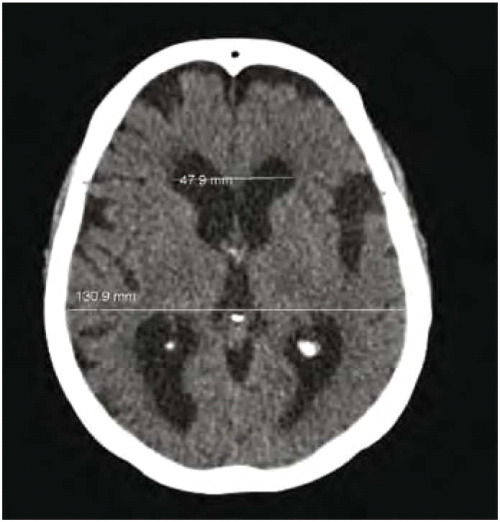

תמונה 2. תהודה מגנטית למח בשקלול T2 במישור סגיטלי בנבדק עם NPH

התמונה מדגימה flow void (חץ) באזור האקוודוקט ע"ש סילביוס